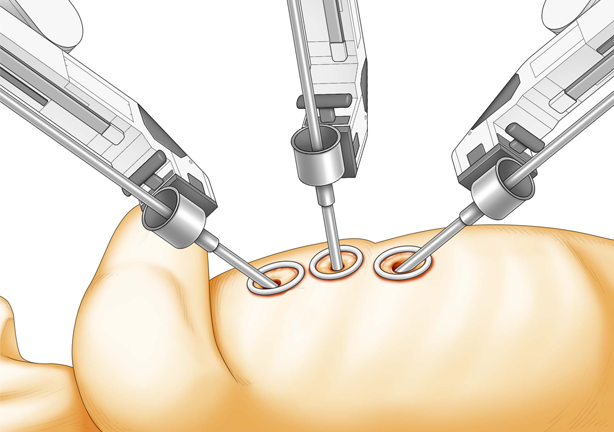

1cmほどのキーホール(鍵穴)を3カ所開け、ロボットアーム(鉗子)や内視鏡カメラを挿入して手術を行います。3D内視鏡カメラにより、術野を鮮明な3D映像で患部を拡大視野で捉えることができ、ロボットの鉗子をミリ単位の操作してオペを遂行します。

“ダビンチ”キーホール手術は、手術支援ロボット“ダビンチ(da Vinci Surgical System)”を用いたロボット手術です。開胸することなく、骨を切らず、数カ所のキーホールからすべての操作が遂行できるので、術中の出血が少なく、術後の痛みも軽く、また大きな傷が残らないため美容的にも優れています。従来のように人工心肺などを使用して遂行していた手術が“ダビンチ(da Vinci Surgical System)”の出現により劇的に変化し、術後経過や術中の体への負担が軽減できるようになりました。“ダビンチ(da Vinci Surgical System)”のような内視鏡手術の進歩は心臓だけでなく、すべての領域で目覚ましい発展を遂げています。現在では珍しいものでは無く標準の手術方法として認められる傾向にあり、新たなアプローチとして広い分野で採用されています。

そして、手術における傷を1cm程度にし、患者様が早期に社会復帰ができるよう支援するロボット手術は多くの領域で採用が進んでいます。例えば甲状腺疾患などでも、「傷を小さく」「首ではなくわきの下から患部にアプローチ」することが可能になり、患者様の身体への負担を大きく減らすことができるようになりました。特に傷が残ることへの不安を覚えやすい女性の方にとっては大きな変革と言えるでしょう。このように従来の問題を克服し、より良い治療を実現できるのが、ロボット手術の魅力の一つだと言えます。

完全内視鏡下外科手術で「切開しない治療」を実現

手術支援ロボット“ダビンチ”を使用したロボット手術は、骨を切らずに小さな傷口のみでオペを行い、出血量・痛みの減少を実現します。早期の社会復帰が可能な手術です。

手術支援ロボットのダビンチによる手術や小切開手術が可能な場合がございます。ダビンチの手術は小さな3つの穴から手術を行うため従来の方法より痛みや傷の感染、出血量が軽減。